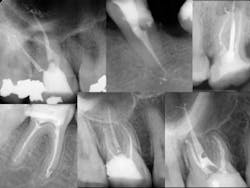

Once all of the canals are found, I will go through the series of Sybron Twisted Files size 25 tapering from 0.10 to 0.80 to 0.60 to 0.40. The 0.40 file should reach the working length for most canals. On a large palatal or distal canal, the 0.60 TF will usually reach working length. After which, using the crown-down technique with the Brasseler EndoSequence rotary files, instrument each canal until files reach the working length. Once instrumentation is complete, take a P.A. with gutta-percha to confirm instrumentation to working length. I find it much easier to take working length films with gutta-percha rather than files (which may fall out, bend, or separate)

Calcified canals

When approaching a calcified canal or a canal that’s curved and narrow, the C-files become a very important instrument. Sometimes, if the curve is very significant, I won’t use rotary files at all.

- Separated file — The dreaded separated file is probably the most common complication clinicians encounter when performing root canals. There was a time when those broken instruments made me wish I never started the root canal in the first place. These days, I will work to bypass the file and get a predictable result.

To prevent file fractures, irrigate after every file. Also, apply gentle pressure and never push when instrumenting a canal.

If a file separates, take a P.A. film immediately to figure out where in the canal the file is lodged. Most likely there’s a curve that the file could not negotiate. Start negotiating the canal with a 6 or 8 C-file. The goal is to engage the space around the file where you can instrument next to it. It could take an extra 30 or 40 minutes and lots of irrigation, but you should be able to negotiate the canal with a 15 file to working length. Irrigate very well and obturate. Sometimes the file will actually exit the orifice of the tooth when irrigating. But it’s perfectly reasonable to use the file as part of the fill.